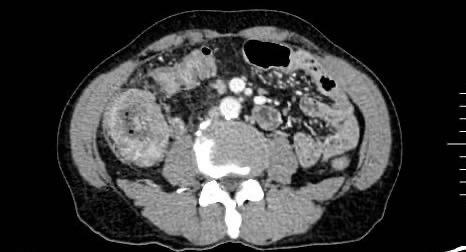

摘要:背景与目的 结肠横纹肌样癌(RCC)是一种极为罕见且高度侵袭性的肿瘤,常伴广泛转移,预后极差,目前尚无标准化治疗方案。本研究报告1例RCC,并结合既往文献总结其临床、病理及分子特征,以期提高对该病的认识。方法 回顾性分析中南大学湘雅医院收治的1例RCC的临床表现、影像学、病理及免疫组化特征,同时检索并整理国内外已报道的36例RCC,汇总其临床资料、免疫表型、基因变异、治疗方式及随访结果。结果 患者为71岁男性,表现为腹胀、腹痛及排便改变,影像及内镜提示升结肠肿瘤并不完全性梗阻。行腹腔镜右半结肠癌根治术,病理示低分化RCC,侵透浆膜层,淋巴结转移4/21;免疫组化示角蛋白AE1/AE3(+)、vimentin(+)、CDX2(-)、CK20(-),Ki-67(80%+),INI1表达保留;基因检测显示KRAS突变、BRAFV600E野生型。患者因经济原因未行放化疗,术后3个月出现腹膜转移而死亡。纳入的37例患者,男女比1.3∶1,平均年龄66岁,62%病变位于右半结肠;多数表现为低分化、横纹肌样细胞占主导,97.06%表达vimentin,100.00%表达角蛋白AE1/AE3,约85.71% CDX2(-);基因中65.00%伴BRAFV600E突变,约22.73%存在KRAS突变;MMR状态中pMMR占60.71%,dMMR占39.29%。多数患者行手术治疗,但78.79%在术后1年内死亡,中位生存6.0个月,仅少部分接受辅助化疗或免疫治疗者生存超过1年。结论 RCC具有高度恶性、生长迅速、易发生早期转移及复发的特点,对常规化疗反应差。其发生可能与肿瘤去分化、INI1缺失及BRAF/KRAS通路异常激活相关。手术仍为主要治疗方式,但术后应积极评估免疫治疗、生物制剂和放疗等综合策略的潜在价值。需进一步研究其分子机制及有效治疗手段。